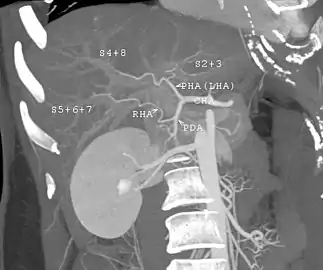

Technique

Before transplantation, liver-support therapy might be indicated (bridging-to-transplantation). Artificial liver support like liver dialysis or bioartificial liver support concepts are currently under preclinical and clinical evaluation. Virtually all liver transplants are done in an orthotopic fashion; that is, the native liver is removed and the new liver is placed in the same anatomic location.[7] The transplant operation can be conceptualized as consisting of the hepatectomy (liver removal) phase, the anhepatic (no liver) phase, and the postimplantation phase. The operation is done through a large incision in the upper abdomen. The hepatectomy involves division of all ligamentous attachments to the liver, as well as the common bile duct, hepatic artery, hepatic vein and portal vein. Usually, the retrohepatic portion of the inferior vena cava is removed along with the liver, although an alternative technique preserves the recipient's vena cava ("piggyback" technique).

The donor's blood in the liver will be replaced by an ice-cold organ storage solution, such as UW (Viaspan) or HTK, until the allograft liver is implanted. Implantation involves anastomoses (connections) of the inferior vena cava, portal vein, and hepatic artery. After blood flow is restored to the new liver, the biliary (bile duct) anastomosis is constructed, either to the recipient's own bile duct or to the small intestine. The surgery usually takes between five and six hours, but may be longer or shorter due to the difficulty of the operation and the experience of the surgeon.

The large majority of liver transplants use the entire liver from a non-living donor for the transplant, particularly for adult recipients. A major advance in pediatric liver transplantation was the development of reduced size liver transplantation, in which a portion of an adult liver is used for an infant or small child. Further developments in this area included split liver transplantation, in which one liver is used for transplants for two recipients, and living donor liver transplantation, in which a portion of a healthy person's liver is removed and used as the allograft. Living donor liver transplantation for pediatric recipients involves removal of approximately 20% of the liver (Couinaud segments 2 and 3).